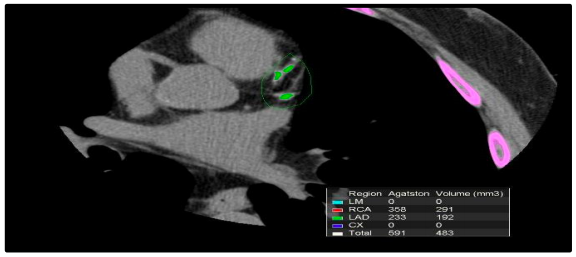

Mulher de 47 anos, diabética, assintomática, comparece à consulta trazendo o escore de

cálcio mostrado abaixo.

Resultado com escore de cálcio- 591 Agatston, no percentil 90. De acordo com a Diretriz Brasileira de Dislipidemia de 2017,